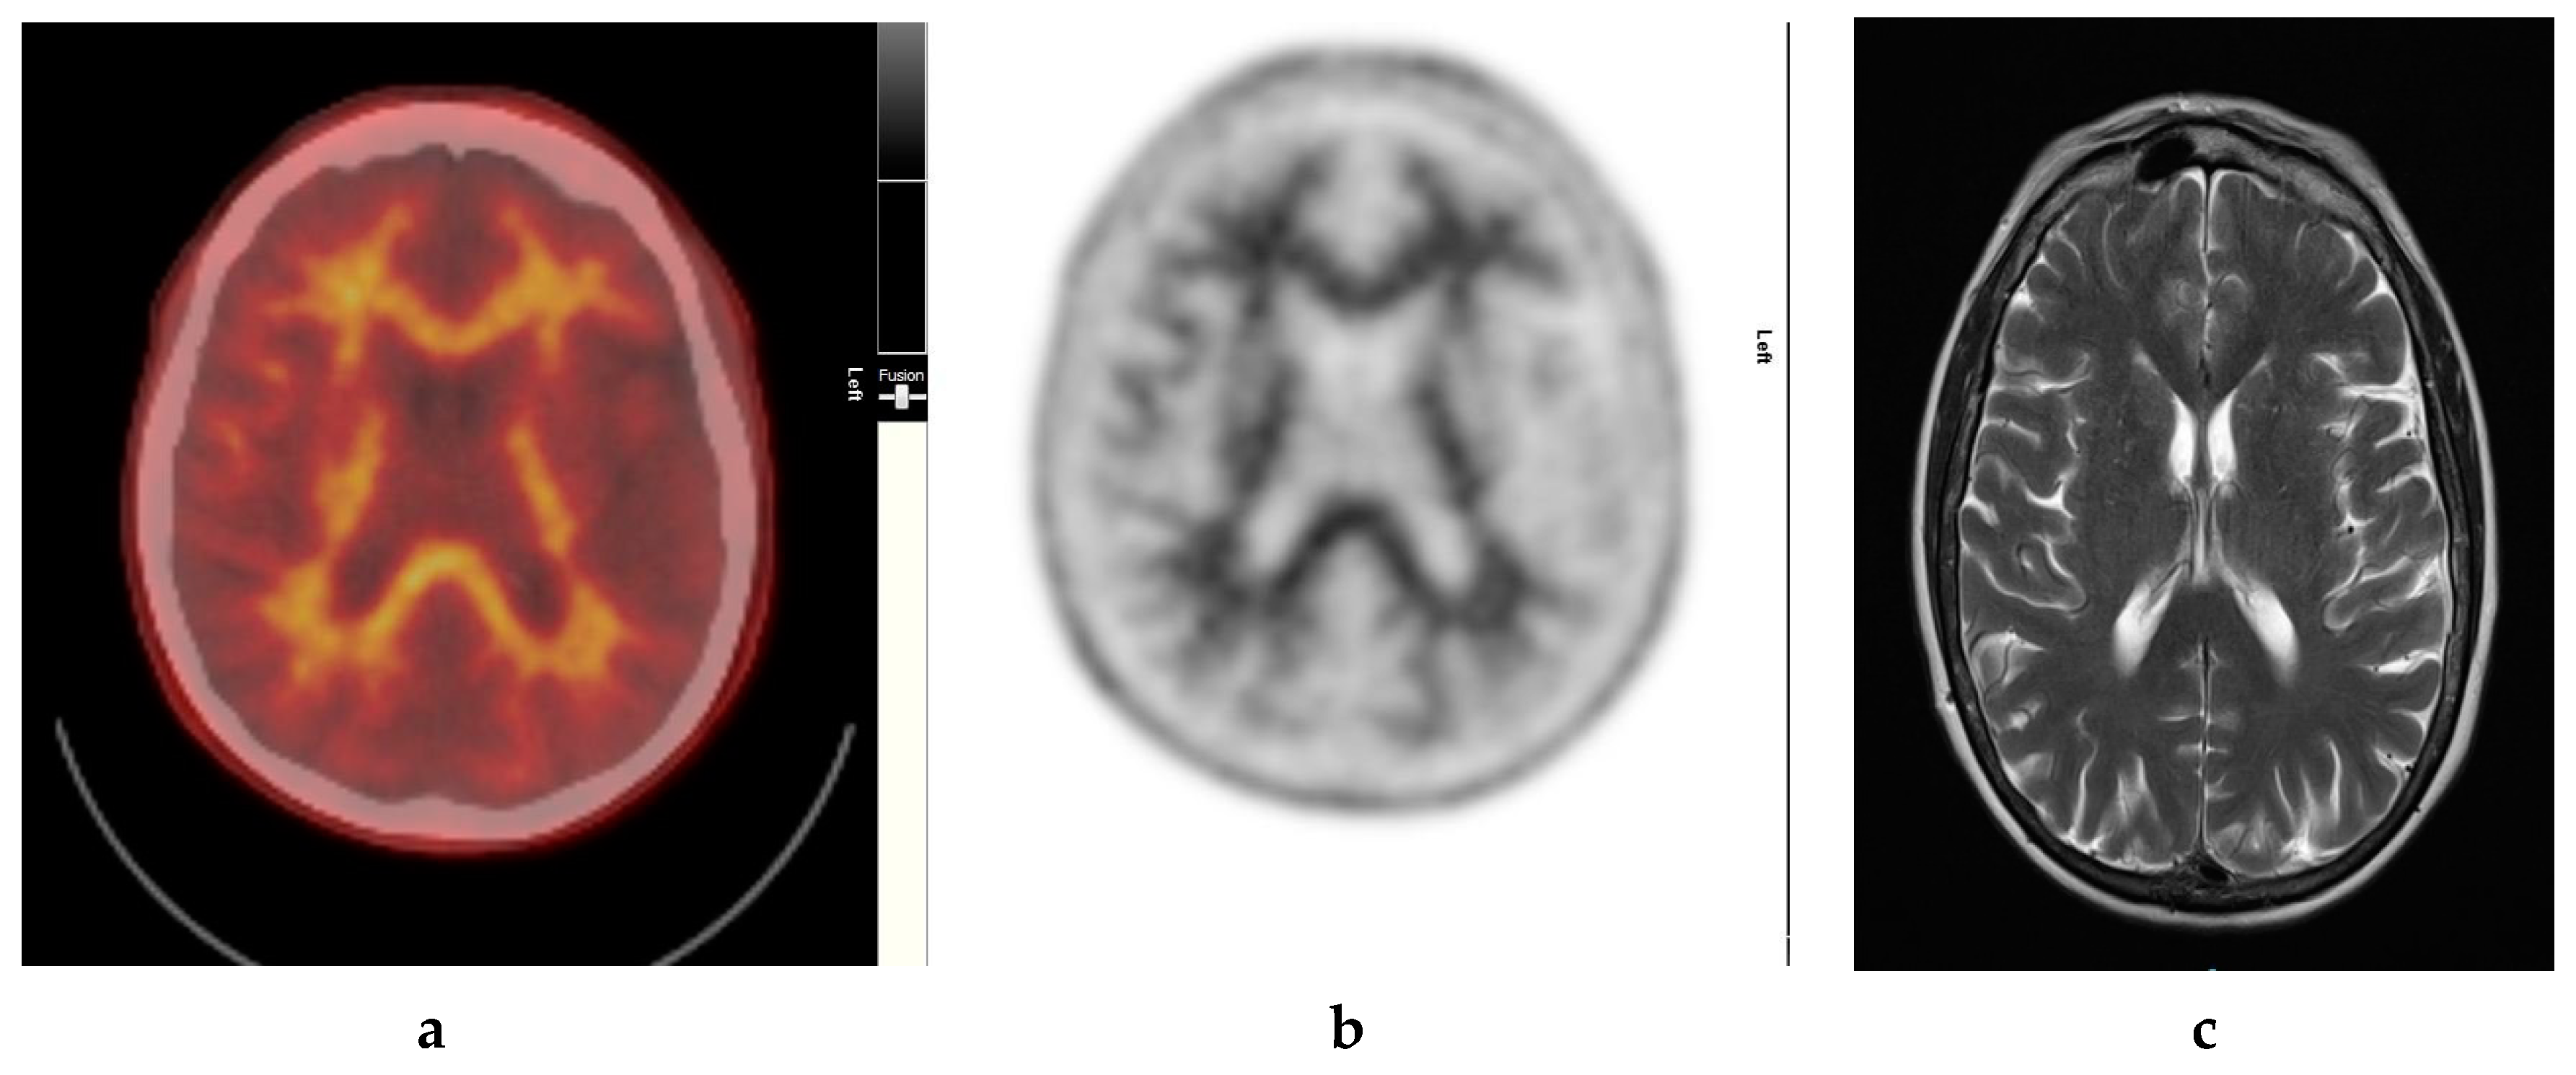

It also demonstrates excellent specificity to Aβ detection and has favorable pharmacokinetics, whereby it is quickly cleared from the blood circulation with approximately 10% of the radiotracer remaining at 20 min post injection. The radiotracer readily enters the brain and 20 min post injection, a clear separation can be seen between individuals with and without significant cerebral amyloid deposition (Figure 1).

Normal study. Sixty-seven year old female patient with deteriorating cognition and multiple vascular risk factors for assessment for vascular dementia. (a) and (b) [18F]FBP shows good contrast between grey and white matter in all sections of the brain with no obvious evidence of beta amyloid plaque disease. This suggests that the diagnosis/development of Alzheimer’s disease is less likely. (c) MRI brain scan (multiplanar and multi sequence acquisitions) shows no significant T2 signal abnormality or restricted diffusion to suggest space occupying lesion, infarction, or ischemic change. (figures are courtesy RLBUHT Hospital database).